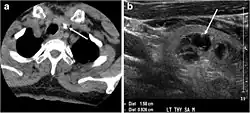

Fig. 4. A 45-year-old male patient presented with anterior mediastinal metastatic PTC lesions and occult primary on imaging. Histopathology examination of the resected thyroid gland revealed micro-foci of PTC; the largest, in the isthmus, measured 4 mm. a transverse greyscale ultrasound of the thyroid demonstrates homogeneous gland with normal echogenicity and size. No focal lesion or micro-calcifications. b Non-enhanced CT scan obtained as part of PET/CT examination shows a heterogeneous, large, relatively dense anterior mediastinal mass (white arrow) with peripheral calcification (arrowheads). Thyroid gland has normal CT appearance with no abnormal FDG uptake (not shown).[1] -

Fig. 7. A 51-year-old female patient post total thyroidectomy for PTC with elevated thyroglobulin measurement. an Axial non-enhanced CT scan of the neck at the level of the thyroid bed demonstrates a well-defined, rounded, homogenously dense soft tissue situated between the trachea and left internal jugular vein (white arrow). b Transverse ultrasound image of the neck demonstrates a well-defined, homogeneous, hypoechoic soft tissue nodule measuring 6 mm (white arrow) with no detected micro-calcifications. Biopsy showed a predominantly residual normal thyroid tissue with micro-foci of PTC.[1] -